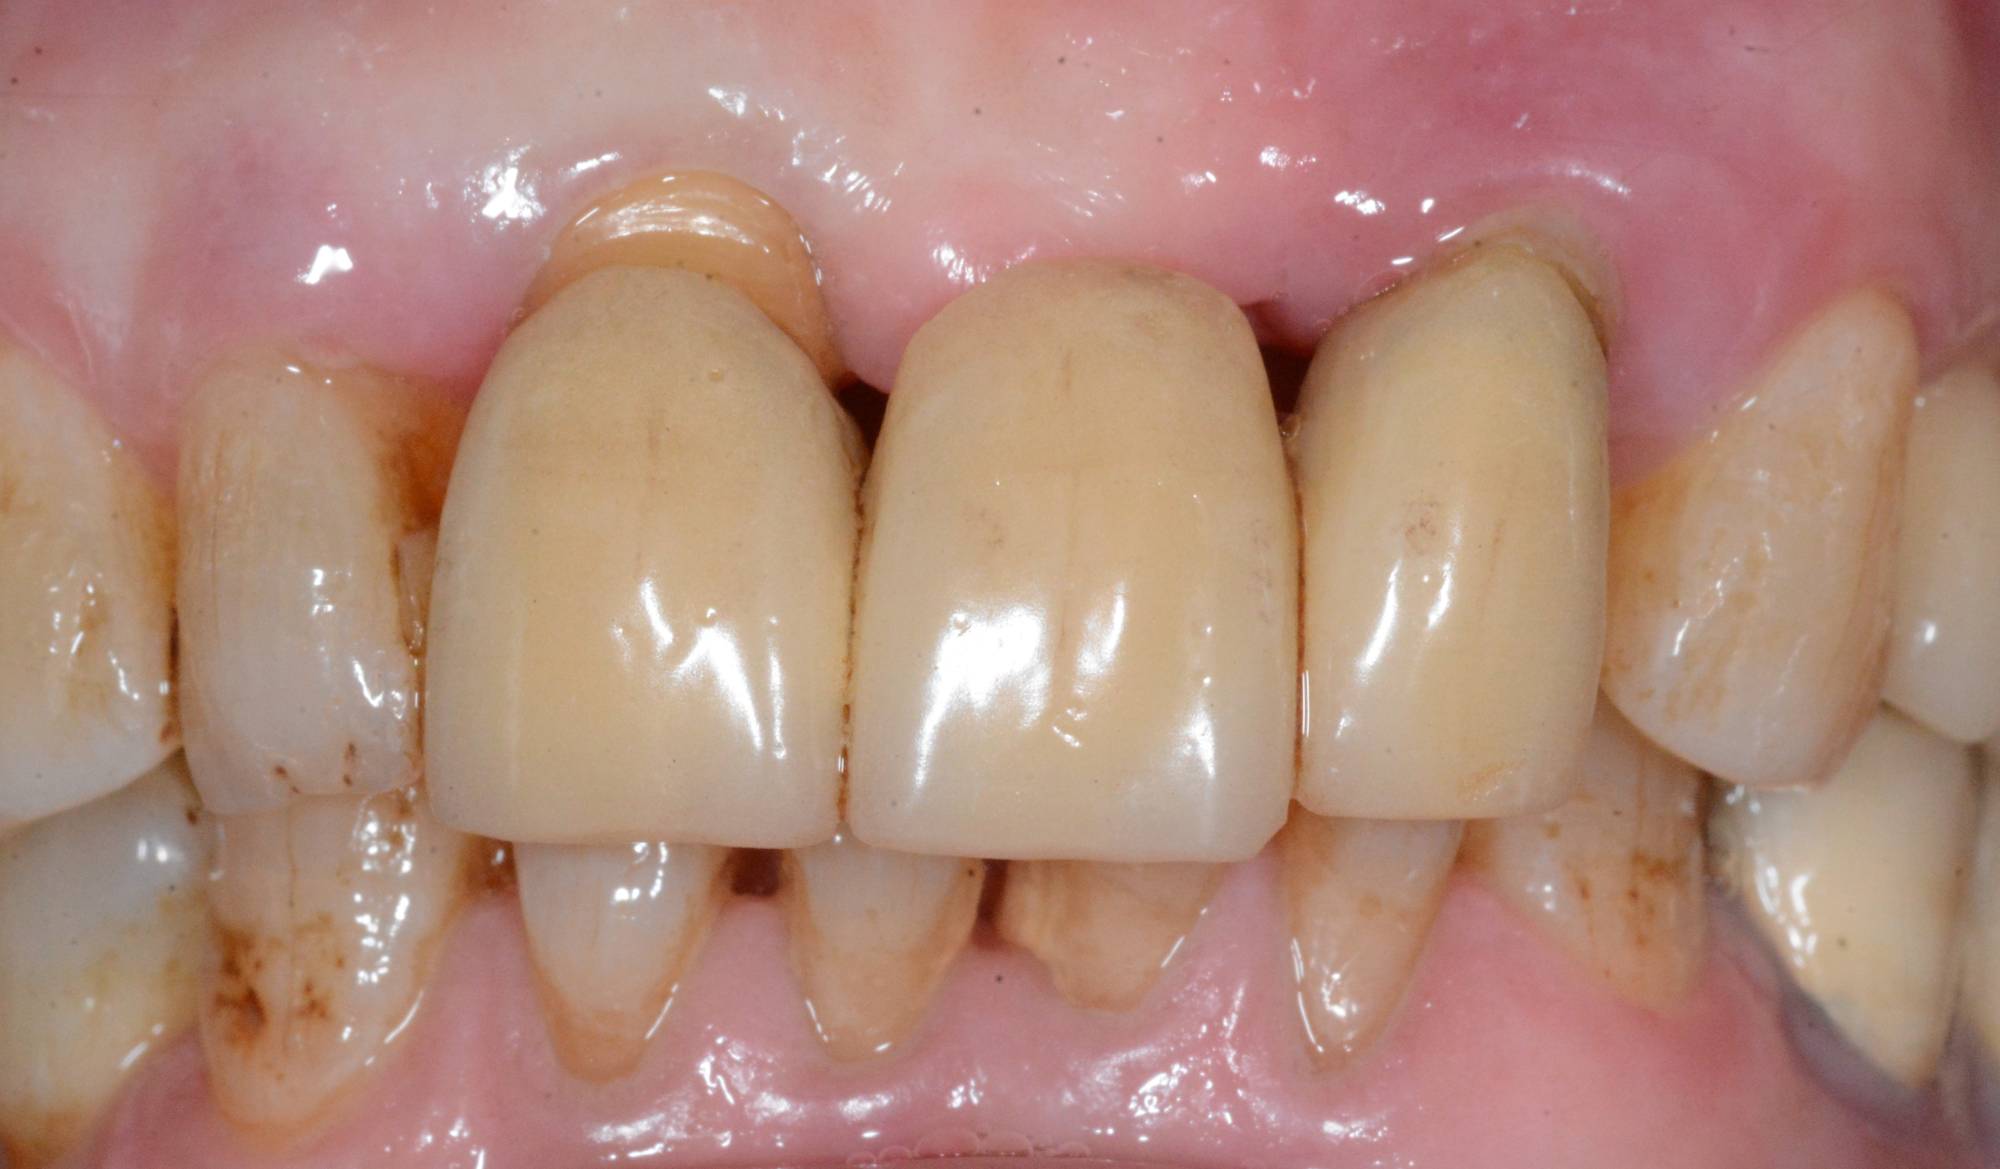

Guarda la foto successiva. Quel ponte di 3 denti sugli incisivi si muoveva così tanto che le rendeva la vita un dramma. Ho dovuto estrarle il vecchio ponte, inserire due impianti osteointegrati e fare quello che noi dentisti chiamiamo “rigenerazione ossea guidata”, per ricostruirle l’estetica naturale che vedi nella prima foto. Solo nella terza, la radiografia, puoi vedere cosa c’è dentro, al posto del suo denti ormai persi.